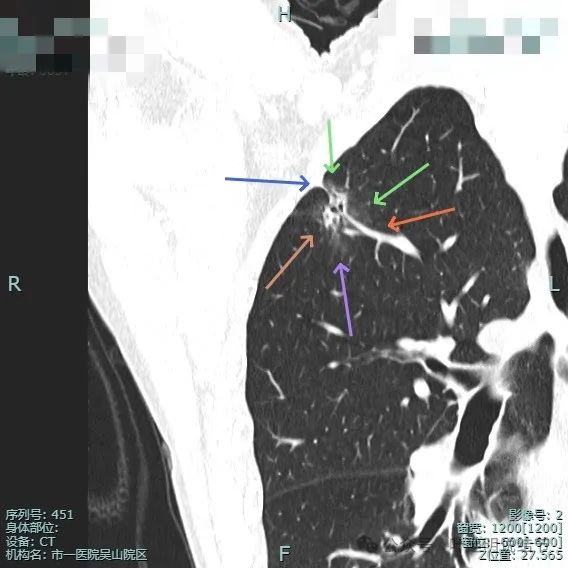

病灶混合密度,毛刺典型,灶内密度紊乱,表面分叶,有较多小空泡征,胸膜略有牵拉。

血管进入病灶,磨玻璃成分较淡,边缘不平毛糙多毛刺、胸膜有牵拉,表面分叶征明显。

实性成分较多,表面不平,磨玻璃部分较淡,血管进入与穿行,胸膜牵拉可见,距其不远有次病灶也是淡磨玻璃密度,轮廓较清,也考虑是肿瘤范畴的,当然风险仍低。

表面不平分叶,实性成分明显,灶内细支气管扩张。